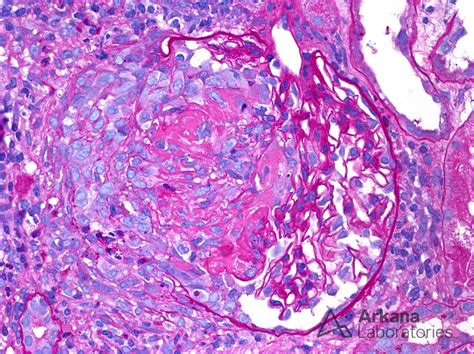

Infective Endocarditis Gn

Infective Endocarditis Gn, or Infective Endocarditis of the native heart valves, is a specific form of the condition that affects the heart's natural valves. This type of Infective Endocarditis is more common than Infective Endocarditis affecting prosthetic valves and can occur in individuals with no prior history of heart disease. The diagnosis and treatment of Infective Endocarditis Gn follow similar principles to those of Infective Endocarditis in general, with a focus on early detection and appropriate antibiotic therapy.